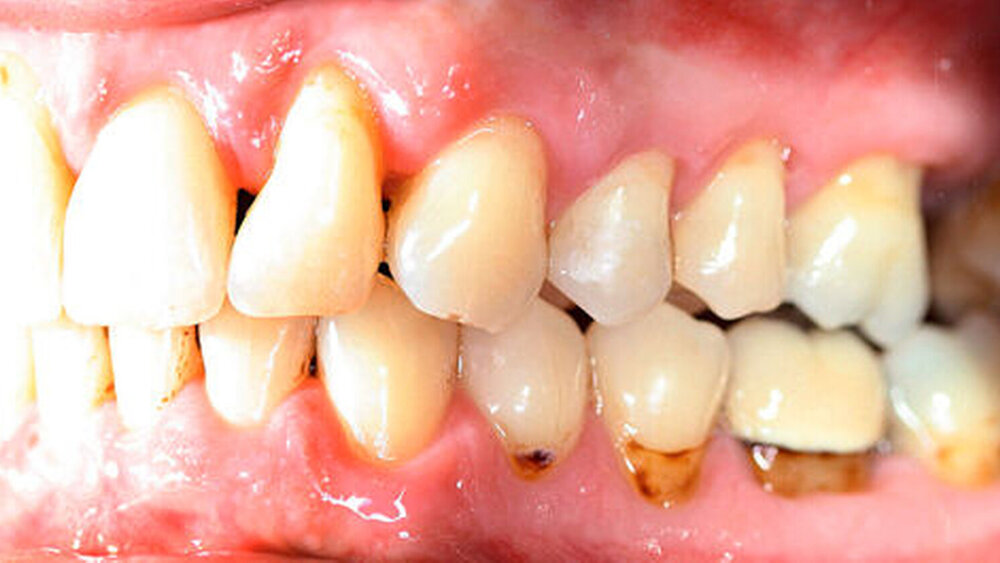

Kieferorthopädisch imponierte beidseits eine neutrale Verzahnung bei einem tiefen Biss von 5 mm – bedingt durch die Verlängerung beider Frontzahngruppen. Besonders Zahn 11 zeigte eine erhebliche Verlängerung und Protrusion mit einer sagittalen Frontzahnstufe von 5 mm. Sowohl die Frontzähne im Ober- als auch im Unterkiefer wiesen eine lückige Beziehung zueinander auf (Abbildung 1).

Um einen kompletten Lückenschluss im Oberkiefer zu ermöglichen, musste im Unterkieferfrontzahnbereich zusätzlich zur Derotation und Positionierung der Zähne – insbesondere Zahn 41 – von approximaler Schmelzreduktion, kurz ASR , Gebrauch gemacht werden, um einer Tonn`schen Diskrepanz entgegenzuwirken (siehe dazu Abbildung 7 auf Seite xy).

Eine zusätzliche Behandlung mit einem Schmelzmatrixprotein, gesteuerter Geweberegeneration oder Ähnliches lehnte der Patient ab. Die reine Intrusion von Zahn 11 konnte mit 2,5 mm beziffert werden, während Overjet und Overbite jeweils 2 mm und 3 mm betrugen. Die Abbildung 4 zeigt den Zwischenbefund nach zwei Monaten mit den transparenten Schienen.